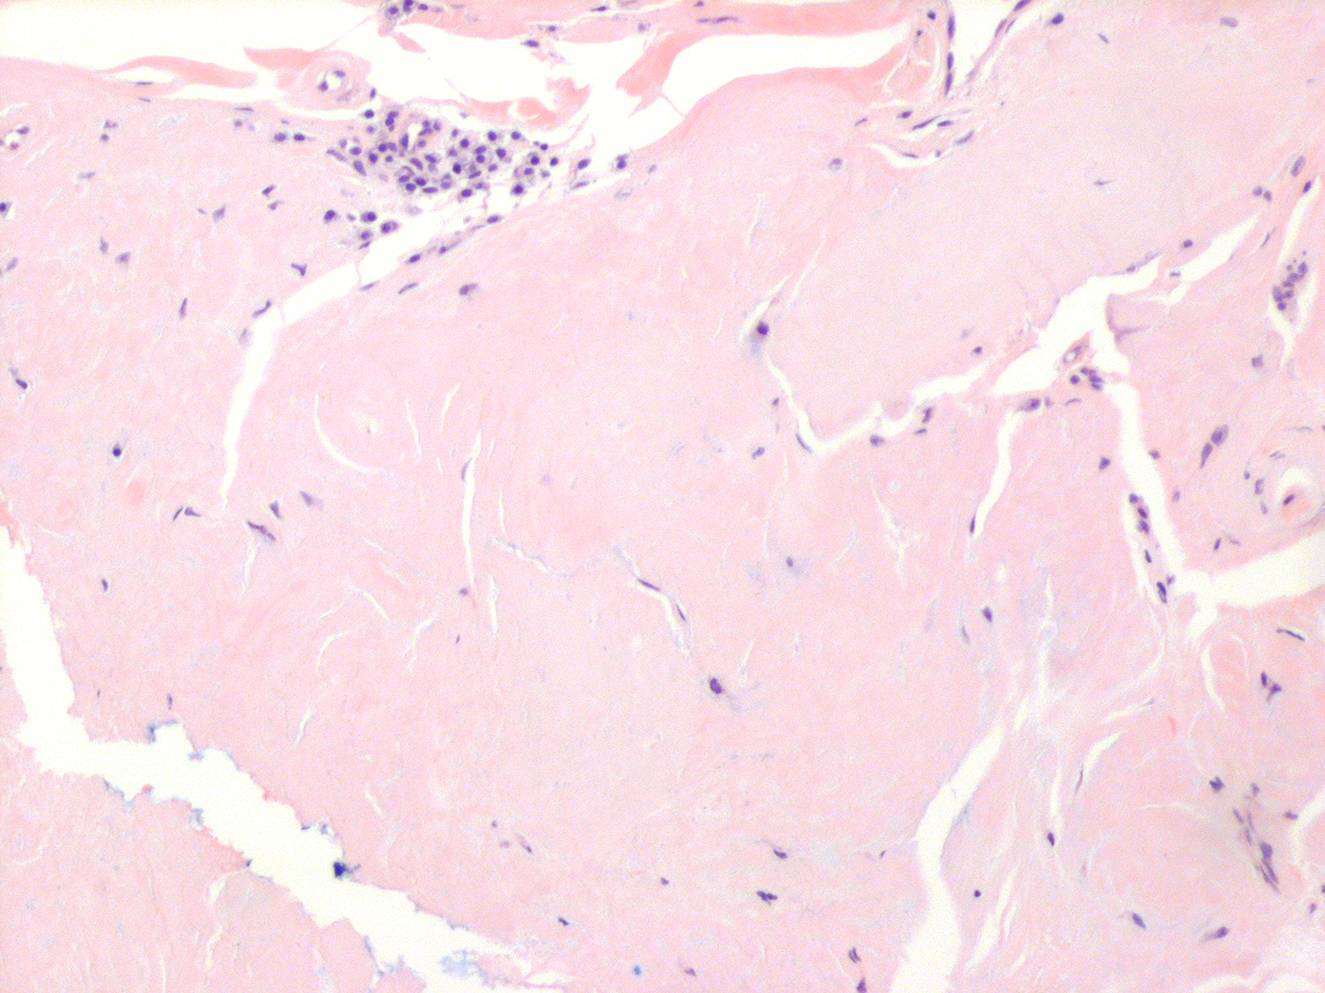

Nodular amyloid =الداء النشواني العقيدي